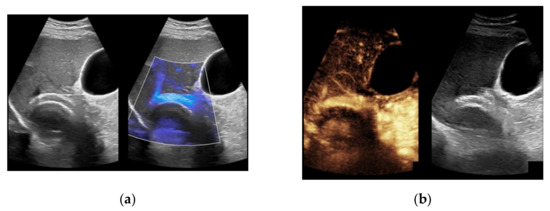

When taking a closer look at the results of the CEUS examinations, 70.8% (n = 75) of the patients showed regular stent perfusion (Figure 4), 17.9% (n = 19) of the patients featured TIPS occlusion (Figure 5) while 6.6% (n = 7) patients had stent thrombosis (Figure 6). In contrast to the results from CDUS, there were no patients with only partial accessibility of the TIPS during CEUS, while the two patients with meteorism also were not assessable during CEUS. The three patients categorized in “others” showed simultaneous findings between CDUS and CEUS (Table 2).

Figure 4.

Same patient as in Figure 1 with continuous flow within the transjugular intrahepatic portosystemic shunt (TIPS) without thrombosis or occlusion using microflow imaging (a) and after administration of contrast agent (b,c).